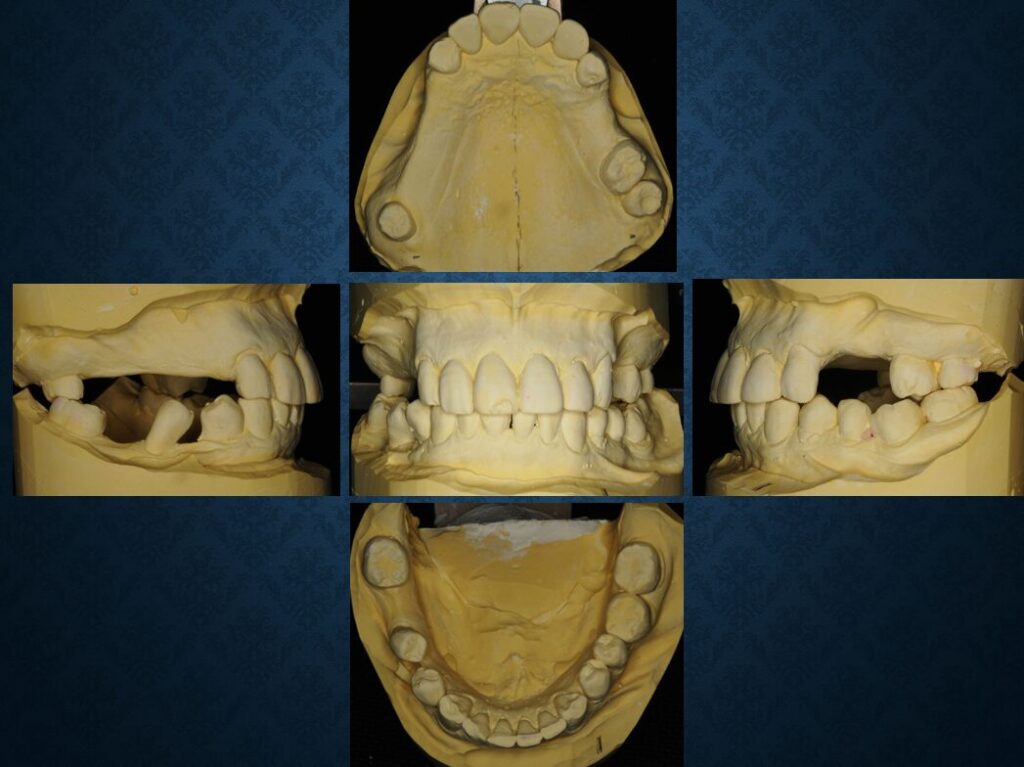

40代フィリピン人男性の方でした。欠損部には入れ歯が入っていました。インプラントに代えて欲しいというご希望でした。職業は会社経営、モデル、英会話教師、ボディービルダー、六本木警察フィリピン語講師、映画俳優など多岐にわたり、日本だけでなく、オーストラリア、台湾、スペインなどを渡り歩いている方でした。多忙を極めていらしたので治療は度々中断しましたが、無事にゴールできました。